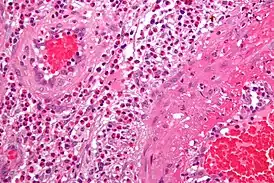

Гистологическое исследование при АНЦА- СВ.

(Уровень доказательности С): Положительные данные биопсии играют большую роль в подтверждении васкулита.

При биопсии слизистой носа у больных ГПА обнаруживают деструктивно- продуктивный васкулит и гигантоклеточные некротизирующие гранулёмы. Биопсия ткани орбиты в случае ГПА с псевдотумором орбиты необходима для дифференциальной диагностики с различными доброкачественными и злокачественными новообразованиями, в частности с IgG- ассоциированным заболеванием. Диагностическая ценность крайне редко выполняемой открытой биопсии легкого значительно выше, чем трансбронхиальной или биопсии слизистой оболочки носа и придаточных пазух. При биопсии кожно- мышечного лоскута у больных ЭГПА обнаруживают картину деструктивно- продуктивного васкулита с эозинофильной инфильтрацией.

Биопсия почки (c обязательным применением иммунолюминисцентной микроскопии) позволяет подтвердить диагноз АНЦА-ГН при наличии фибриноидного некроза капилляров клубочка и артериол, экстракапиллярного пролиферативного ГН с эпителиальными и/или фибро- эпителиальными “полулуниями” в клубочках в сочетании с отсутствием иммунных депозитов в ткани почки. Показаниями к диагностической биопсии почки являются: